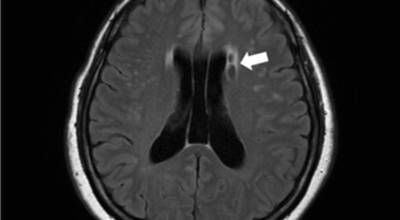

뇌경색 초기증상이 나타나면 가장 중요한 것은 빠른 인지와 빠른 치료예요. 뇌세포는 뇌혈관이 막히는 순간부터 빠르게 손상이 진행이 되고 재생은 어렵기 때문입니다. 뇌와 연관된 질병은 골든타임을 놓치지 않는 것이 제일 중요해요.

큰 뇌혈관이 막힌 경우라면 발생한지 4시간 반 안에 정맥 내로 혈전 용해제를 투여해 막힌 혈관을 뚫어주게 되고 6시간 이내라면 직접 동맥 내 시술을 통해 혈관을 막은 혈전을 직접 제거하는 혈전제거술을 시행하게 되는데요.